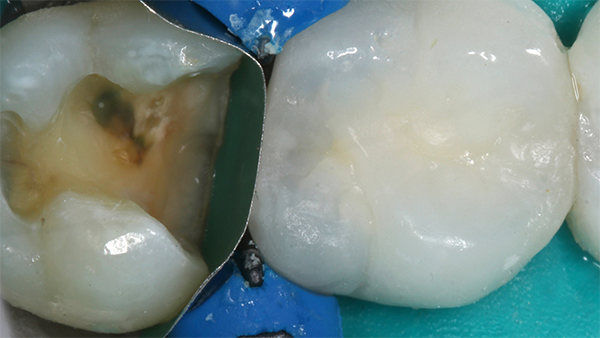

Fig 6. Bulk-fill composite resin for posterior restoration.

Figure 6

Fig 7. Due to the larger quantity with bulk fill, extra attention should be given to ensure the resin is adequately cured.

Figure 7

The bulk-filling technique (Figure 6) emerged several years ago as a replacement for more difficult, time-consuming incremental placement techniques. The advantage of bulk filling is that it allows dentists to place large quantities of composite resin at once.24 However, because of the larger quantities being used, it is important to make sure the resin is adequately cured (Figure 7) in order to prevent white lines at the margins and reduce shrinkage, which could lead to gaps, leakage, cracks, or postoperative sensitivity.25

Research shows that proper use of high-intensity lights will cure a range of 4.5 mm to 9.5 mm of resins, according to Gordon J. Christensen, DDS, MSD, PhD.24 He recommends checking the depth of cure in the light being used with the resin being used through the following procedure: place the quantity of resin normally used about 10 mm high and 5 mm in diameter on a piece of paper; place the light tip directly over the resin and cure the resin for the time normally cured; after curing, scrape the bottom part of the resin sample with an instrument, such as a sharp laboratory knife, and remove the soft resin; continue scraping until the process becomes difficult and one seems to be cutting into the cured resin instead of the soft, partially cured resin; measure the depth of cure. Although Christensen warns this is not a precise test, it will provide some indication of the curing ability of the light being used.